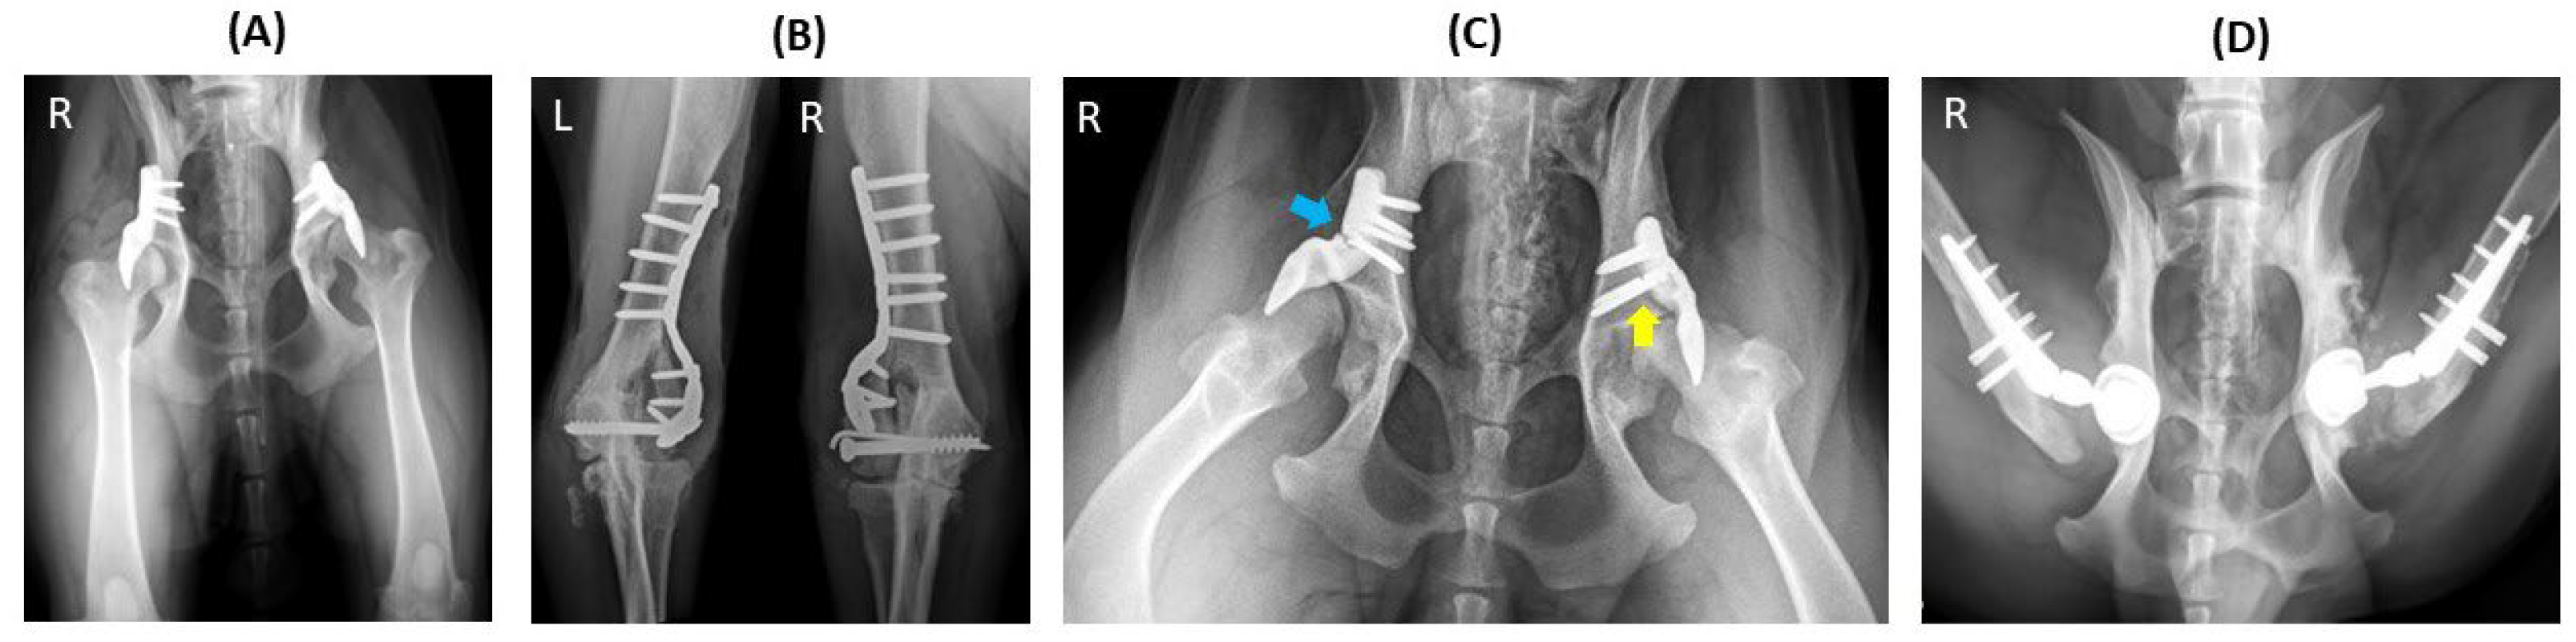

3.5. Complications

3.6. Histopathology and 3D X-ray Microscopy

| Complication | 2 broken screws and severe OA | broken implant and severe OA | 4 broken screws | severe OA | severe OA | septic arthritis | |

| Follow up time until complication (days) | 246 | 178 | 215 | 291 | 291 | 528 | |